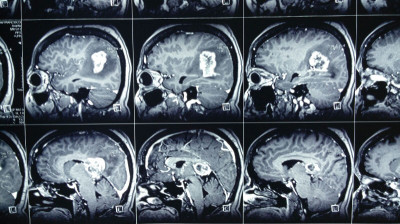

Paciente femenina de 55 años con tumoracion pineal con extencion superior lateral derecha